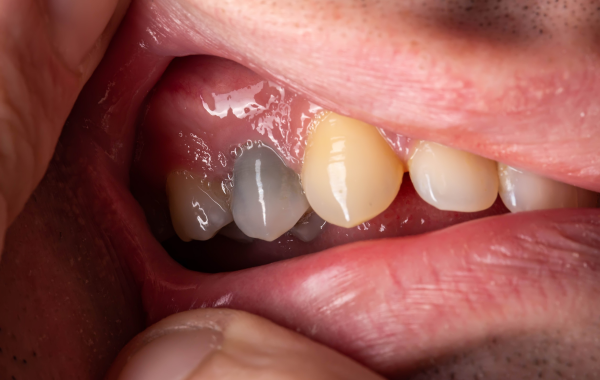

- une décoloration de la dent, qui devient plus grise ou jaunâtre ;

Un traumatisme dentaire, même ancien, peut également être à l’origine de la nécrose. Un choc violent interrompt la circulation sanguine de la dent, entraînant une mort progressive des tissus internes. Les fractures, les obturations anciennes ou les traitements mal adaptés peuvent aussi contribuer à cette dégradation.